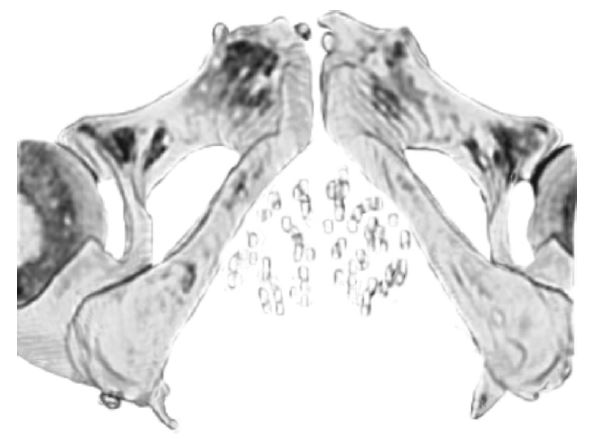

This procedure involves implanting radioactive Iodine-125 seeds directly into the prostate gland. The seeds continuously give off low level radiation for about one year. Each seed is 5mm in length and 0.5mm thick. The seeds are held together in a strand for implanting as can be seen here in the illustration.